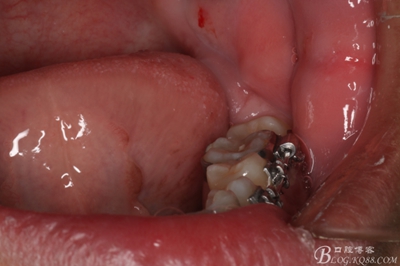

圖16.清理38牙槽窩內(nèi)的囊壁及碎牙片

圖17.   38牙槽窩放入膠質(zhì)銀

18.縫合